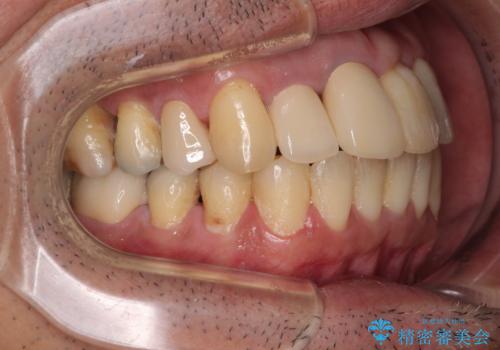

隠れている前歯 インビザライン矯正治療と前歯のセラミック治療

- 隠れるほどに内側に転位しいてる前歯を気にして来院された患者様です。

仕事柄海外出張が多いとのことで、インビザラインにて矯正治療を行うこととしました。

矯正治療後は、前歯や下顎の奥歯など、むし歯治療途中の歯をオールセラミッククラウンにて補綴治療を行うこととしました。

内側に転位していた前歯は、矯正治療では治しきることができませんでしたが、幸いにもオールセラミッククラウンに置き換える予定であったため、希望通りの仕上がりとなりました。